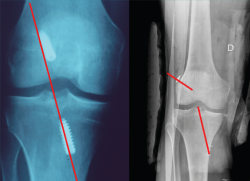

El estudio radiológico recomendado debería incluir proyecciones anteroposteriores y laterales, axiales de rótula, telemétricas de la extremidad inferior y también en posición de Schuss (en carga y con unos 30° de flexión de la rodilla). La radiología simple va a permitir identificar qué técnica quirúrgica se realizó inicialmente y qué material se utilizó para la fijación (Figura 1). La proyección en Schuss permite observar si existen cambios degenerativos en los compartimentos femorotibial interno o externo de la rodilla de forma más precisa que con la radiología simple en decúbito supino. Finalmente, la radiografía telemétrica de las extremidades inferiores va a permitir conocer el eje mecánico de la extremidad. La existencia de deformidades en el plano coronal se ha asociado a un incremento de la solicitación mecánica del LCA y también del riesgo de rotura de la plastia (Figura 2)(21).

Figura 1. Imagen radiológica que permite identificar una técnica de reconstrucción transtibial o “monotúnel” (izquierda) respecto a una técnica anatómica (derecha).